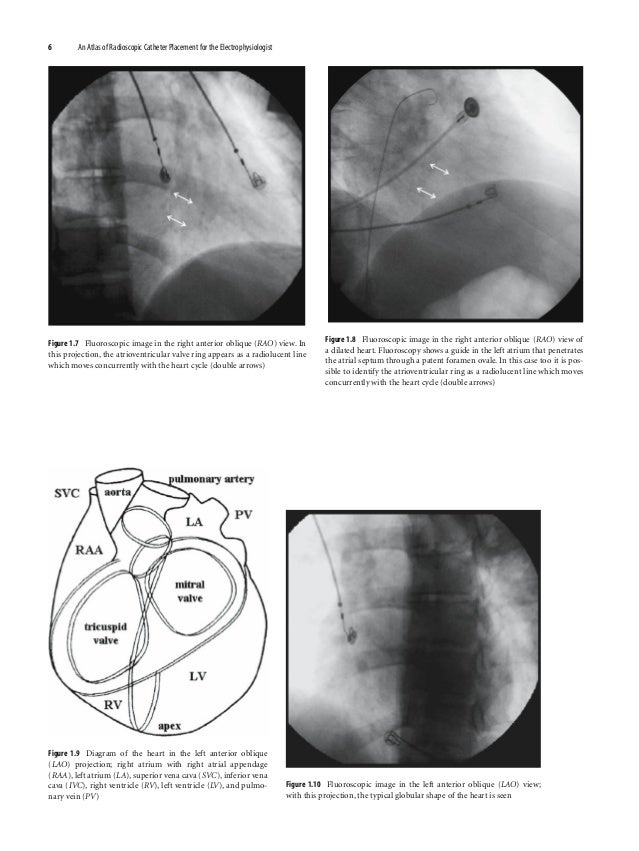

An Atlas Of Radioscopic Catheter Placement For The Electrophysiologist